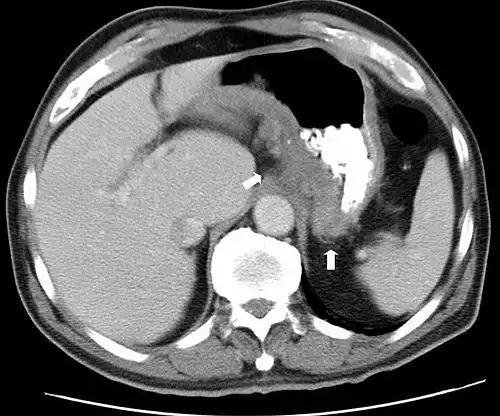

با تجویز سریع کنتراست وریدی در طی سی تی اسکن این جزئیات دقیق تصویری را می توان بازسازی سه بعدی نمود و بدین ترتیب تصاویری از کاروتید، شریان مغزی و کرونری، یا به صورت سی تی آرتریوگرافی و سی تی آنژیوگرافی حاصل نمود. سی تی اسکن است تست انتخابی در تشخیص برخی از شرایط اضطراری و اورژانس مانند خونریزی مغزی، آمبولی ریه ( لخته ای که موجب انسداد در عروق ریه ها شود )، دایسکشن آئورت یا همان پارگی سرخرگ آئورت ( پاره شدن دیواره آئورت )، آپاندیسیت، دیورتیکولیت، و سنگ کلیه می باشد. با ادامهٔ پیشرفت ها و بهبود مداوم در فناوری سی تی اسکن، از جمله سریعتر شدن زمان تصویربرداری و بهبود رزولوشن یا وضوح و تفکیک پذیری تصاویر، دقت و کارایی این روش به طور چشمگیری افزایش یافته و در نتیجه از سی تی اسکن به میزان بیشتری در تشخیص های پزشکی استفاده می شود.